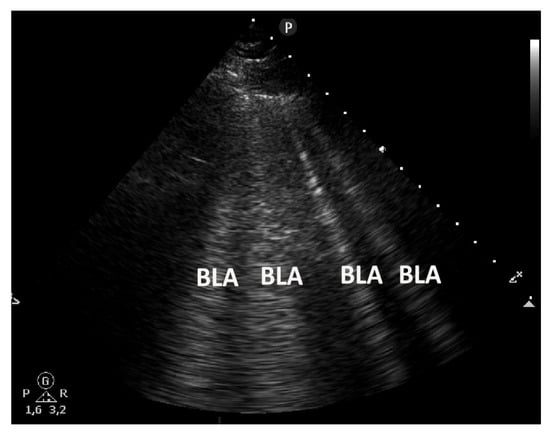

Pulmonary edema evaluation can be accomplished with a sector, convex, or even a linear transducer. Generally, evidence of edema is best seen with a sector probe, worst with a linear probe. Again, tissue harmonics, beam compounding, and any post processing should be turned off. Pulmonary edema manifests itself as a large amount (greater than two per rib interspace) of B-lines. In the supine patient, the thorax is divided into four areas on both sides. Ubiquitous interstitial syndrome has three or more B-lines in the sagittal view between two ribs, with this in two or more areas on both sides [] (Figure 5 and Figure 6).

Figure 5.

A cardiogenic pulmonary edema shows multiple B-line artifacts (BLAs) homogeneously distributed (as a “curtain” of BLA in the center of the image and lateral as individual BLA) bilaterally (evaluated by convex low frequency transducer <5 MHz without interfering presets). They arise from a smooth pleural line, are well defined, hyperechoic, extending indefinitely (at least 10 cm), and moving with lung sliding.

Figure 6.

A cardiogenic pulmonary edema with multiple B lines (BLA) evaluated by sector transducer.